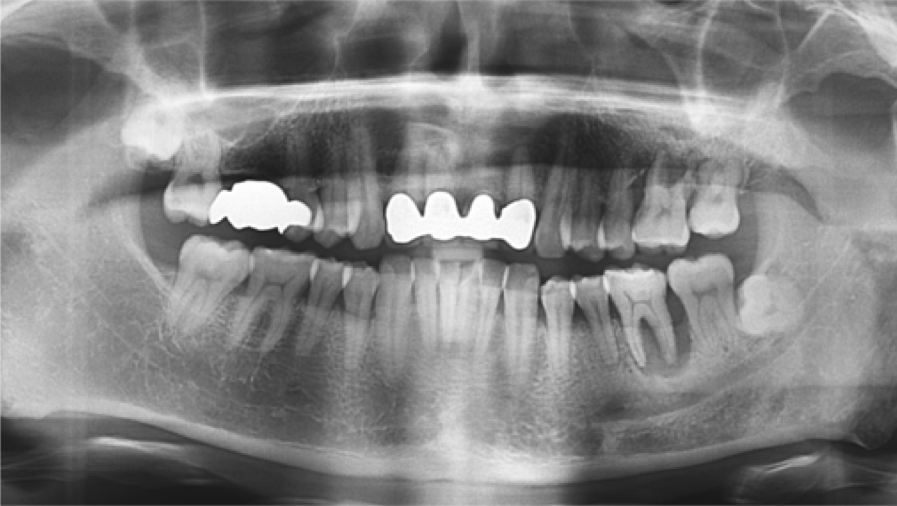

Clinical case: Immediate post-extraction insertion of implant & immediate loading

- Courtesy of Prof. Giuseppe Luongo, Italy -

AnyRidge, immediate loading, single implant, multicenter study, maxillary anterior, Prof. Giuseppe Luongo, single replacement

AnyRidge implant system

Immediate functional loading of single implants: a multicenter study with 4 years of follow-up

/J Dent Res Dent Clin Dent Prospect 2018; 12(1):26-37 | doi: 10.15171/joddd.2018.005

https://www.ncbi.nlm.nih.gov/pubmed/29732018